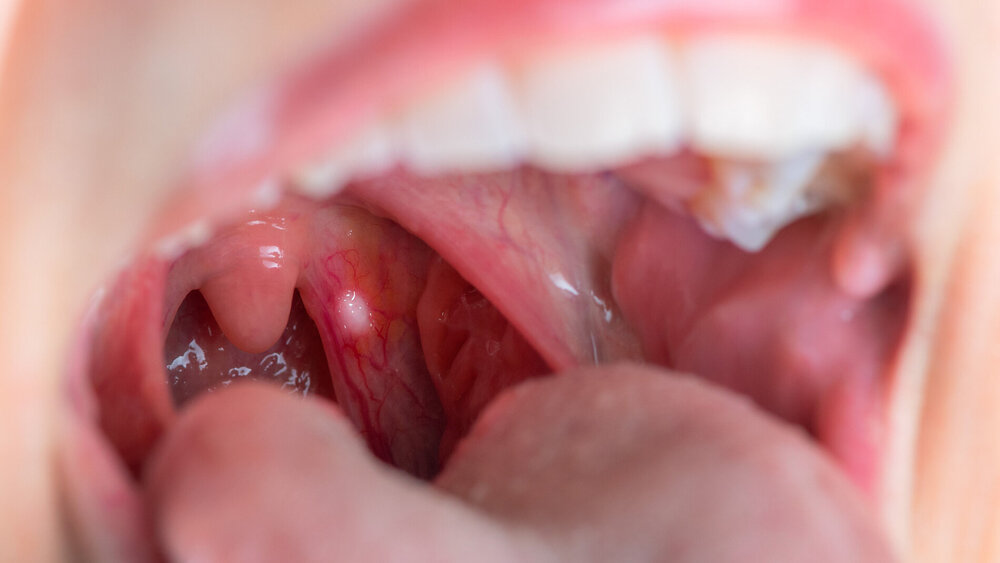

Aggressiver Mundhöhlenkrebs kann im Frühstadium erkannt werden

Mundhöhlenkrebs mit hohem Rezidivrisiko lässt sich durch die Untersuchung der Lymphgefäße des Tumors frühzeitig erkennen, zeigt eine finnische Studie.

Mundhöhlenkrebs ist die häufigste bösartige Tumorerkrankung im Kopf-Hals-Bereich und verursacht jährlich weltweit mehr als 188.000 Todesfälle. Anders als bei vielen anderen Krebsarten kann Mundhöhlenkrebs bereits im Frühstadium tödlich verlaufen. In Finnland, wo die Studie durchgeführt wurde, stirbt bis zu ein Fünftel der Patienten, die im Frühstadium behandelt wurden, später an der Erkrankung, schreiben die Forschenden.

Das Forschungsteam der Universität Turku und des Forschungsprojekts InFLAMES untersuchte anhand von Proben aus Mundhöhlenkrebs-Frühstadien, die von etwa 300 finnischen Patienten stammten, die Eigenschaften verschiedener Abwehr- und Strukturzellen im Tumorgewebe. Durch die Analyse mehrerer unterschiedlicher Proteinmarker machten die Forscher die überraschende Entdeckung, dass einige Tumore eine höhere Anzahl proliferierender Lymphgefäße aufwiesen als normales Gewebe. Diese hohe Anzahl proliferierender Lymphgefäße sagte das Wiederauftreten des Krebses und die Sterblichkeit besser voraus als alle anderen bisher bekannten Risikofaktoren für Mundhöhlenkrebs.